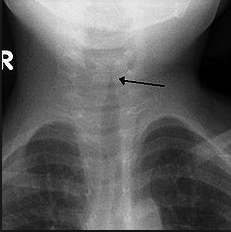

parainfluenza seal: Seal bark cough seen in Croup (caused by parainfluenza virus)

wind blowing in: Inspiratory stridor seen in Croup

church with steeple: Patients with Croup will often have a "steeple sign" on Chest X-ray, narrowing of subglottic region

aka laryngotrachealbronchitis.,